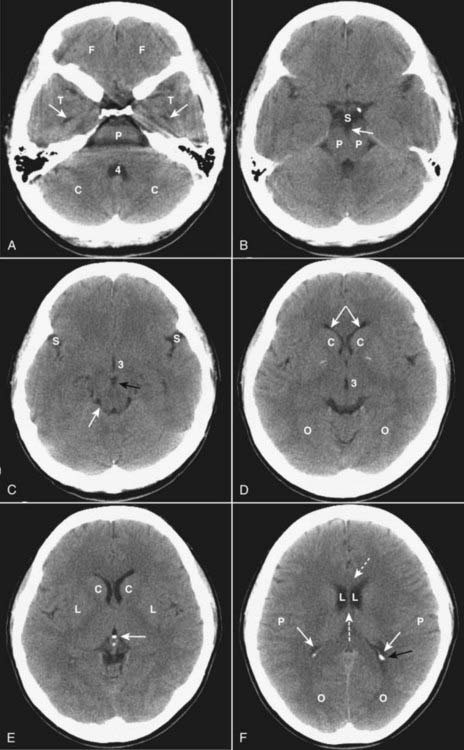

image The normal anatomy of the brain is somewhat easier to understand with CT than MRI (Fig. 25-1).

image In the posterior fossa, the 4th ventricle appears as an inverted U-shaped structure. Like all cerebrospinal fluid (CSF) containing structures, it normally appears black. Superior to the 4th ventricle are the cerebellar hemispheres, inferiorly lie the pons and medulla oblongata. The tentorium cerebelli separates the infratentorial components of the posterior fossa (medulla, pons, cerebellum, and 4th ventricle) from the supratentorial compartment.

image The interpeduncular cistern lies in the midbrain and separates the paired cerebral peduncles (which emerge from the superior surface of the pons). The suprasellar cistern is anterior to the interpeduncular cistern and usually has a five-point or six-point starlike appearance.

image The sylvian fissures are bilaterally symmetrical and contain CSF. They separate the temporal from the frontal and parietal lobes.

image The lentiform nucleus is composed of the putamen (laterally) and globus pallidus (medially). The 3rd ventricle is slitlike and midline. At the posterior aspect of the 3rd ventricle is the pineal gland. Farther posterior is the quadrigeminal plate cistern.

image The corpus callosum connects the right and left cerebral hemispheres and forms the roof of the lateral ventricle. The anterior end is called the genu and the posterior end is called the splenium.

image The basal ganglia are represented by the subthalamic nucleus, substantia nigra, globus pallidus, putamen, and caudate nucleus. The putamen and caudate nucleus are called the striatum.

image The frontal horns of the lateral ventricles hug the head of the caudate nucleus. The two frontal horns are separated by the midline septum pellucidum. The temporal horns, which are normally very small, are more inferior and contained in the temporal lobes. The posterior horns of the lateral ventricle (occipital horns) lie in the occipital lobes. The most superior portion of the ventricular system is formed by the bodies of the lateral ventricles.

image The falx cerebri lies in the interhemispheric fissure, which separates the two cerebral hemispheres, and is frequently calcified in adults.

image The surface or cortex of the brain is made up of gray matter convolutions, which in turn are composed of sulci (grooves) and gyri (elevations). The medullary white matter lies below the cortex.

Figure 25-1 Normal unenhanced CT scans of the head.

A, Frontal lobes (F); temporal lobes (T); temporal horns (solid white arrows); fourth ventricle (4); cerebellum (C); pons (P). B, Suprasellar cistern (S); cerebral peduncles (P); interpeduncular cistern (solid white arrow). C, Sylvian fissures (S); 3rd ventricle (3); interpeduncular cistern (solid black arrow); quadrigeminal plate cistern (solid white arrow). D, Anterior horns of the lateral ventricles (solid white arrows); caudate nuclei (C); 3rd ventricle (3); occipital lobes (O). E, Caudate nuclei (C); lentiform nuclei (L); calcified pineal gland (solid white arrow). F, Genu of corpus callosum (dotted white arrow); lateral ventricles (L); septum pellucidum (dashed white arrow); parietal lobes (P); occipital horn (solid black arrow); calcified choroid plexus (solid white arrows); occipital lobes (O).